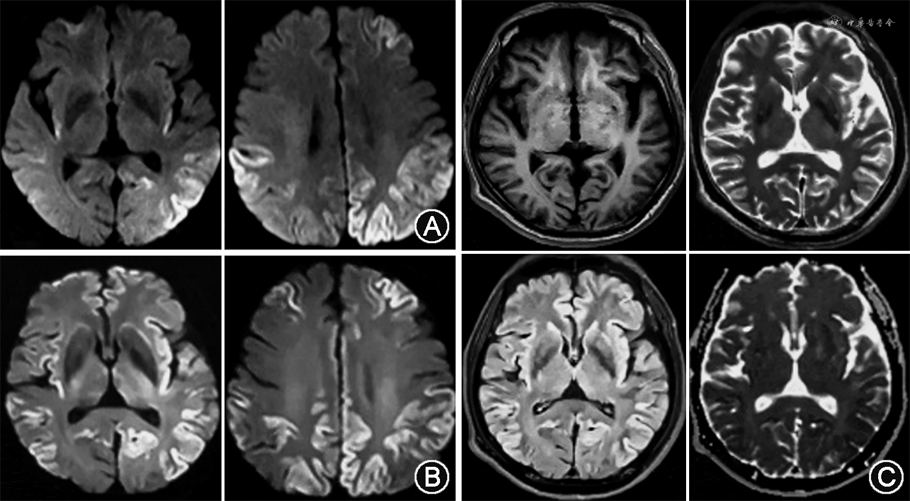

辅助检查:血尿便常规、凝血、肝肾功能、梅毒螺旋体抗体、艾滋病病毒抗原及抗体初筛、乙型肝炎相关抗原及抗体、丙型肝炎抗体、叶酸+维生素B12、抗核抗体谱+抗磷脂抗体谱+系统性血管炎相关抗体谱、常见肿瘤标志物均未见明显异常。毒物筛查未见异常。血抗神经抗原抗体检测:抗N-甲基-D-天冬氨酸受体抗体、抗谷氨酸脱羧酶抗体、抗电压门控钾离子通道抗体及副肿瘤综合征相关抗体Ri、Hu、Yo等免疫检查均未见异常。2020年3月及6月2次行头颅MRI示双侧大脑半球皮质多处花边征并逐渐增多,DWI及FLAIR序列出现高信号(图1)。头颅MRA未见异常。2020年3月外院脑电图报告未见异常。2020年8月于我院复查脑电图提示异常:左颞叶为著不规则慢波;左颞少量尖波(图2)。